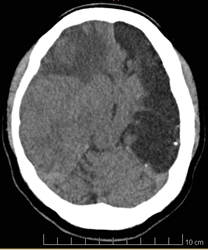

AutoresA nivel de la región frontal derecha se evidencia una zona focal de comportamiento heterogéneo predominantemente hipodensa con zonas centrales mal definidas de hiperdensidad, asociada a efecto de masa, con borramiento de los surcos corticales y pérdida de la diferenciación entre sustancia gris y sustancia blanca. La lesión descrita mide aproximadamente 36×34 mm en sus mayores ejes anteroposterior y transversal, considerándose un posible absceso cerebral versus un tumor cerebral (Figura 2).

Se aprecia zona de densidad heterogénea predominante hipodensa que ocupa el giro frontal medio derecho, condiciona a borramiento de surcos corticales, pérdica de diferenciación sustancia gris sustancia blanca y desviación de las estructuras de la línea media a la izquierda, con desplazamiento del tecer ventrículo